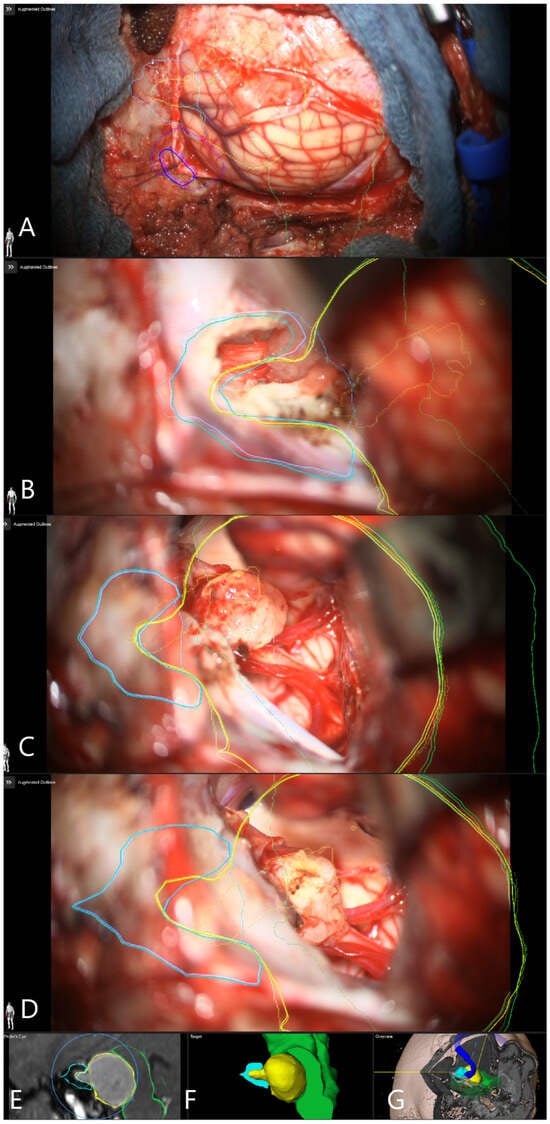

Illustrative Cases